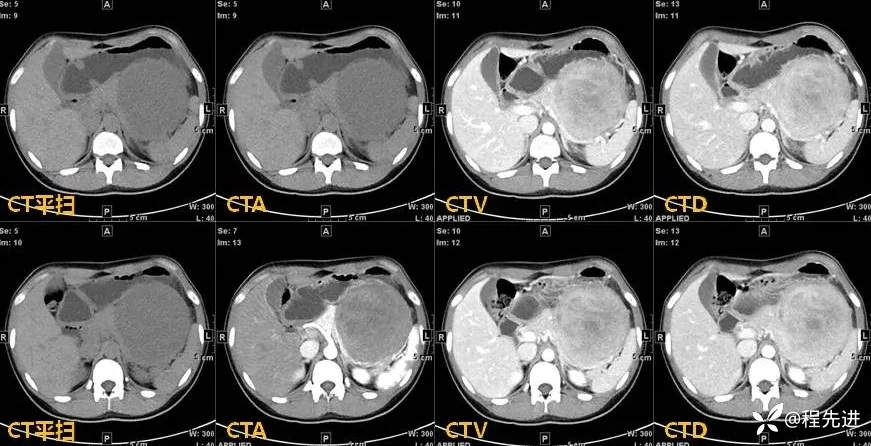

【现病史及既往史】:患者4天前于外院行CT检查发现胰腺肿物,胰胃间隙见一肿物,大小约108mmx103mmx122mm,考虑胰腺实性假乳头状瘤可能性大,无伴发热、畏寒,无恶心、反酸,无呕血、黑便。患者起病以来,一般情况可,无头晕、头痛,无心悸、气促,无腹泻、便秘,无排陶土样大便。精神可,胃纳、睡眠差,尿量如常,尿色淡黄,大便规律,体重未见明显改变。

影像检查: